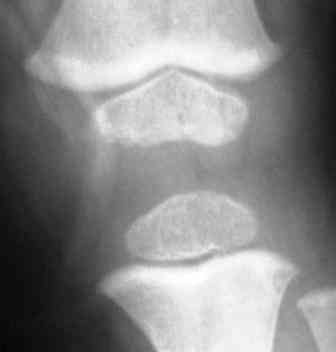

Уважаемый Евгений! Спасибо за обстоятельный совет. Обязательно сделаю КТ или МРТ. Неоднородность структуры зоны роста я, к сожалению, не заметил. По-моему, возникают ассоциации с механизмом развития избыточной антеверсии шейки бедра. Но, все-таки у меня остается впечатление «сжатости» метафизов, особенно бедра.

Для иллюстрации привожу пример из «Нормальной рентгеноанатомии костно-суставной системы детей». В. И. Садофьева. ЛЕНИНГРАД «МЕДИЦИНА» 1990